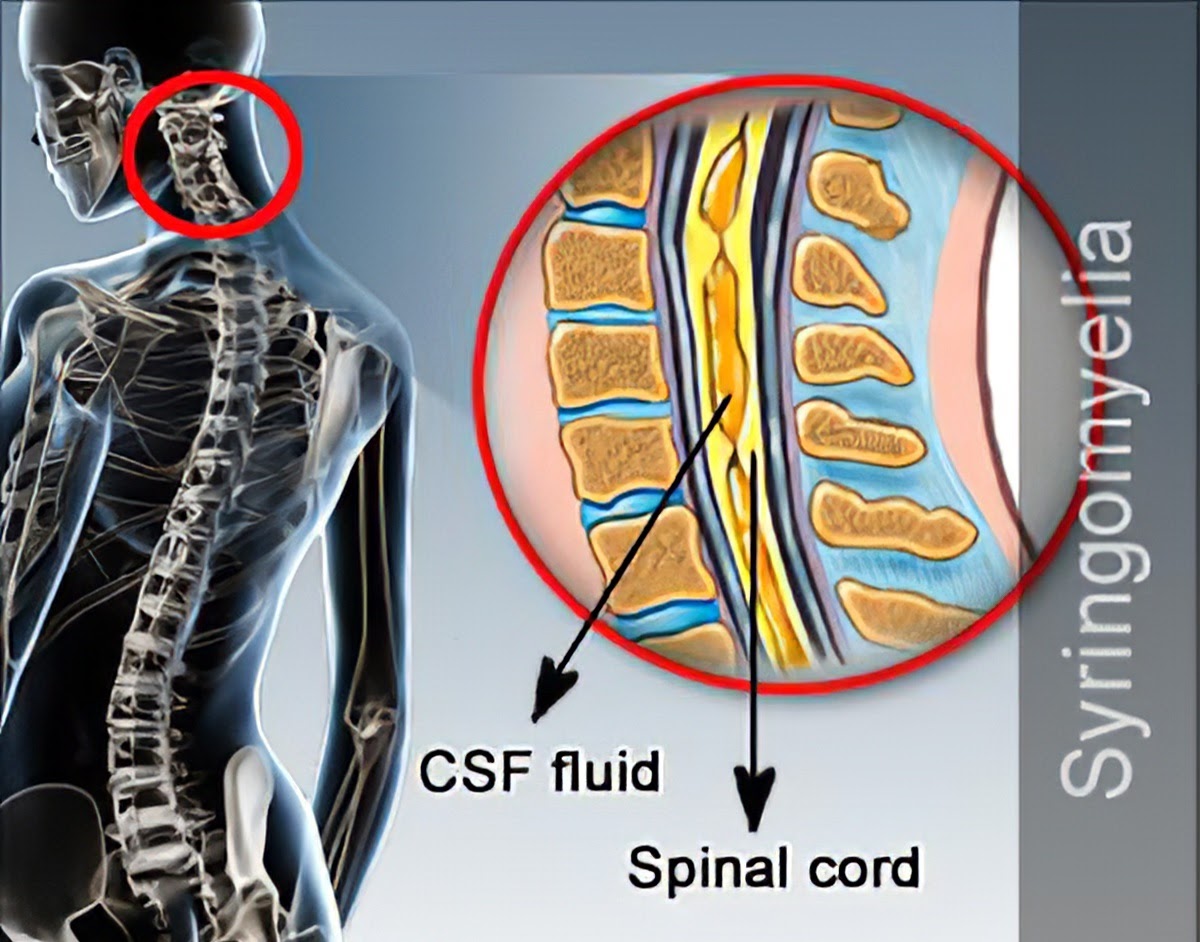

Theo các chuyên gia, bệnh rỗng tủy là do ở trong đoạn tủy sống hình thành một hốc rỗng ở trung tâm của chất xám chứa dịch não tủy. Dịch não tủy tích lại hình thành các khoang hoặc nang hốc phát triển lớn dần và gây huỷ hoại tuỷ, chèn ép dây thần kinh, khiến bệnh có biểu hiện là những rối loạn vận động, rối loạn cảm giác và dinh dưỡng. Bệnh thường được phát hiện tình cờ khi thăm khám các bệnh lý liên quan hoặc khi có các triệu chứng như đau mỏi cổ vai gáy, tê bì tay, mất cảm giác yếu cơ, teo cơ, mất phản xạ gân cơ, mất cảm giác đau hoặc nóng lạnh đặc biệt là ở bàn tay.

Được biết, bệnh rỗng tủy (Syringomyelia) là bệnh mạn tính không thường gặp ở tủy sống với tỷ lệ mắc 8,4/100 000 và thường gặp ở độ tuổi 20-50 tuổi.. Bệnh có thể gặp ở vùng cổ, ngực và thắt lưng, tuy nhiên tỷ lệ gặp nhiều nhất nằm ở ranh giới giữa tủy cổ và tủy ngực.

Rỗng tủy do hình thành trong tủy hốc chứa dịch tích lại phát triển dần gây đè ép, tổn thương tủy. (ảnh minh họa)